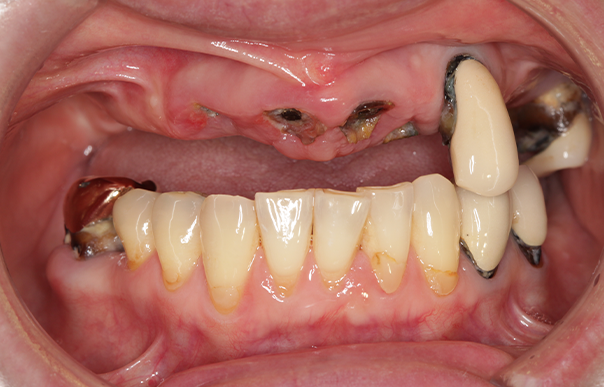

入れ歯をやめて好きなものを食べられるようになりたい。短期間で治療したい【抜歯即時オールオン4】